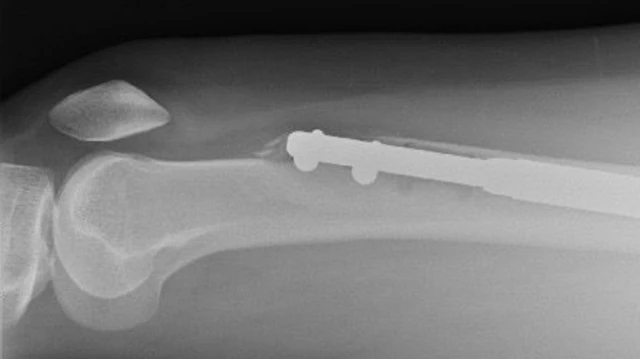

આ પ્રક્રિયામાં દુ:ખાવો થાય જ છે કારણ કે પગનું હાડકું બે ભાગમાં તોડીને વચ્ચે ધાતુનો સળિયો લગાવવામાં આવે છે.

ધીમેધીમે હાડકાંના બંને ભાગ વચ્ચે લાગેલી ધાતુની લંબાઈ વધારવામાં આવે છે જેથી કરીને દર્દીની લંબાઈ વધે.

સામાન્ય રીતે હાડકાંઓનાં બંને ભાગ ફરીથી જોડાય છે અને તેમની વચ્ચેની ખાલી જગ્યાને ભરે છે. અહીં માત્ર શરૂઆત થાય છે પણ તેનું ઑપરેશન ખૂબ જટિલ હોય છે.

બીજા દિવસે જ્યારે સ્કૅનિંગ કરવામાં આવ્યું ત્યારે ઈલેનની આશંકા સાચી સાબિત થઈ. તેમના ડાબા પગની ખીલી હાડકાને વીંધીને બહાર આવી ગઈ હતી. તે પગના ઉપરનાં ભાગનાં હાડકાંને તોડીને બહાર આવી ગઈ હતી. આ શરીરનું સૌથી મજબૂત હાડકું હોય છે.

છ સપ્તાહ બાદ કરાયેલા સ્કૅનમાં તેમને માલુમ થયું હતું કે એમના જમણા પગનાં હાડકાં વધતાં અટકી ગયાં. આ પગમાં ફીમરના બે ટૂકડા રૉડથી જોડાયેલા હતા.